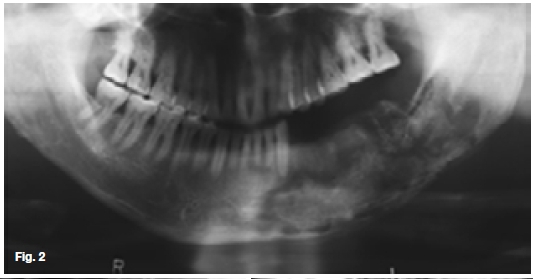

The upper two figures show a case in which there are facial scars of a recurring infection while the pantomo-graph shows ill-defined multilocular radiolucencies with enlargement of the trabecular spaces, suggestive of the presence of a chronic osteomyelitis affecting the hemi-andible on the left side. There are also features demonstrating the formation of sequestra. The case shown in the lower figures started after an assault which had caused a fracture at the angle of the left mandible. A tooth in line of the fracture was removed and since then a draining sinus had developed which showed signs of healing after the removal of sequestrum. In both cases a diagnosis of chronic actionomycotic osteomyelitis of the mandible was made, a rare condition found in 10% of all cervicofacial actinomycosis cases. When it occurs, the radiographic changes are not characteristic. Actionomycosis is a specific infectious disease, primarily caused by the organism Actinomycis Israeli. It affects men twice as frequently as women and is most often encountered in the 20-50 year age groups. The cervicofacial type of actinomycosis is by far the most common, with pulmonary and abdominal actino-mycosis occurring less frequently. However, because of its variable clinical manifestations and difficulty in isolating the causative agent, the diagnosis is often delayed. The actinomycotic infection is not a pure infection; it probably is a result of a synergism between microbes of the ray fungus group and other anaerobic microbes. Clinically, the infection has a prolonged course. The first sign is the appearance of a red to dark blue, nodular infiltration, often located within the skin of the subman-dibular area or angle of the jaw. Untreated, the infection spreads along anatomical planes, producing a hard infiltrate with simultaneous occurrence of draining abscesses. The exudate may contain small yellow granules, termed "sulphur granules", which consist of colonies of actinomyces which tends to be diagnostic. Enlargement of regional lymphnodes is seldom observed and the general status of the patients is unimpaired.